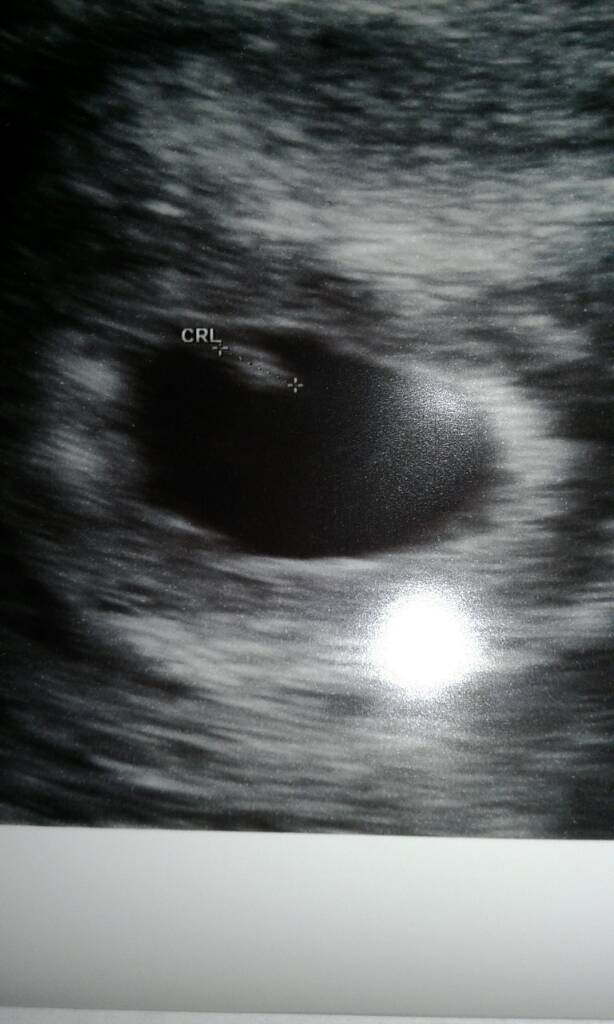

Już po wizycie;) Lekarz w szoku z powodu przyrostu bety 270% w ciągu 48h, ale okazało się ze dzidziuś jest sztuk jeden ;) choć mówi ze zobaczymy następnym razem bo A nuż się schował drugi hahah żarty się trzymają Pana doktora. Powiedział ze przygotuje się do mojej ciąży :) Ciąża jest prawidłowa, 5tydz i 6dni tak jak wychodzi z terminu OM. Termin porodu 10.02.2017 . Poród mi załatwi w innym szpitalu i jego znajomego i tam bedzie wszystko przygotowane.